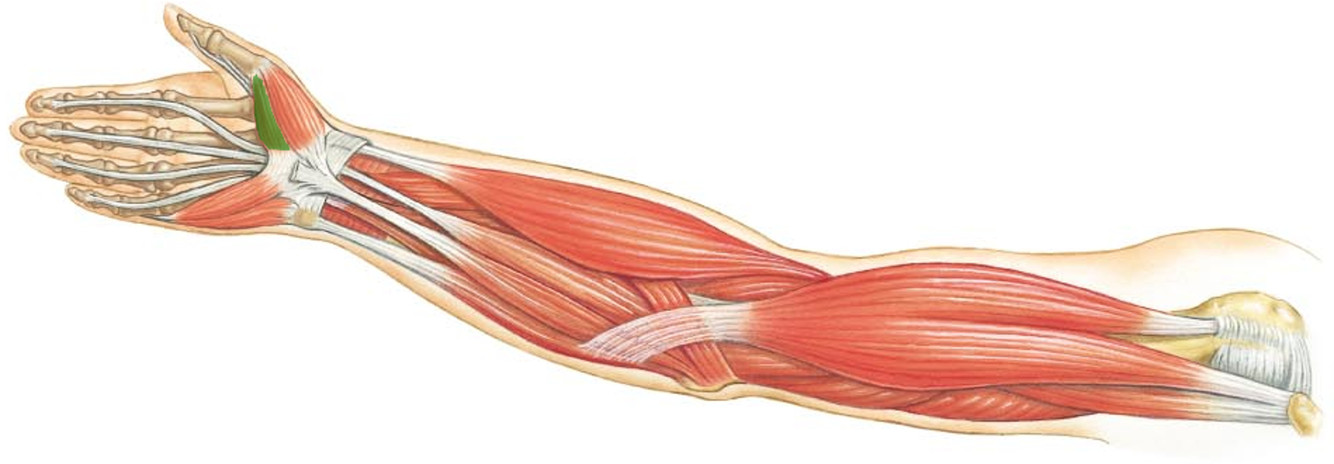

What is the innervation of this muscle?

Muscle - Flexor pollicus brevis

Median nerve